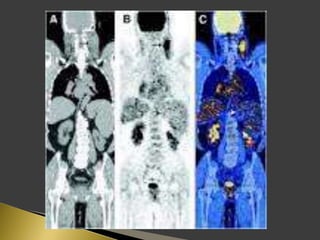

 PET using the radio-labeled glucose analog 18F-FDG has great

importance in lymph node imaging.

 PET supplies a semi-quantitative metabolic characterization of

tissues that may help to predict tumor behavior.

 The sensitivity and specificity of 18F-FDG PET for identification

of lymph node metastases on a neck level-by-level basis were

higher than those of CT/MRI.

 The incorporation of functional information derived from PET

has the potential factor to improve prognostic stratification and

treatment planning for patients.

 Patients were instructed to fast for 6 h before the PET study.

 18F-FDG was administered intravenously.

 For PET/CT scans, oral contrast was administered to patients

during the uptake time.

 No IV contrast material was administered for CT scans.

 Head to mid thigh scans were obtained for all patients.

 PET and CT images were acquired 50 min after the injection of

18F-FDG.

 PET, CT, and fused PET/CT images were available for review

and were displayed in axial, coronal, and sagittal planes.

 PET data were displayed as non-corrected and attenuation-

corrected images as well as in a rotating MIP.

 Area of increased 18F-FDG uptake with intensity higher than

that of surrounding tissues and did not correspond to the

physiologic bio-distribution of the radiotracer, were defined as

positive.

 18F-FDG activity only in areas of the physiologic tracer bio-

distribution or no sites of increased uptake were considered

negative.

 The highest activity within a region of interest was measured.

 The standardized uptake value (SUV) was determined as the

highest activity concentration per injected dose per body weight

(kg).

 18F-FDG uptake was graded visually on the following 5-point

scale:

 0-definitely benign, no uptake.

 1-probably benign, 2.3 (range, 1.4–4.0).

 2-equivocal, 2.6 (range, 1.4–4.4).

 3-probablymalignant, 3.5 (range, 2.1–7.9).

 4-definitely malignant, 6.6 (range, 2.6–24.5).

 SUV of 3.1 was used as the cutoff for positive PET results.